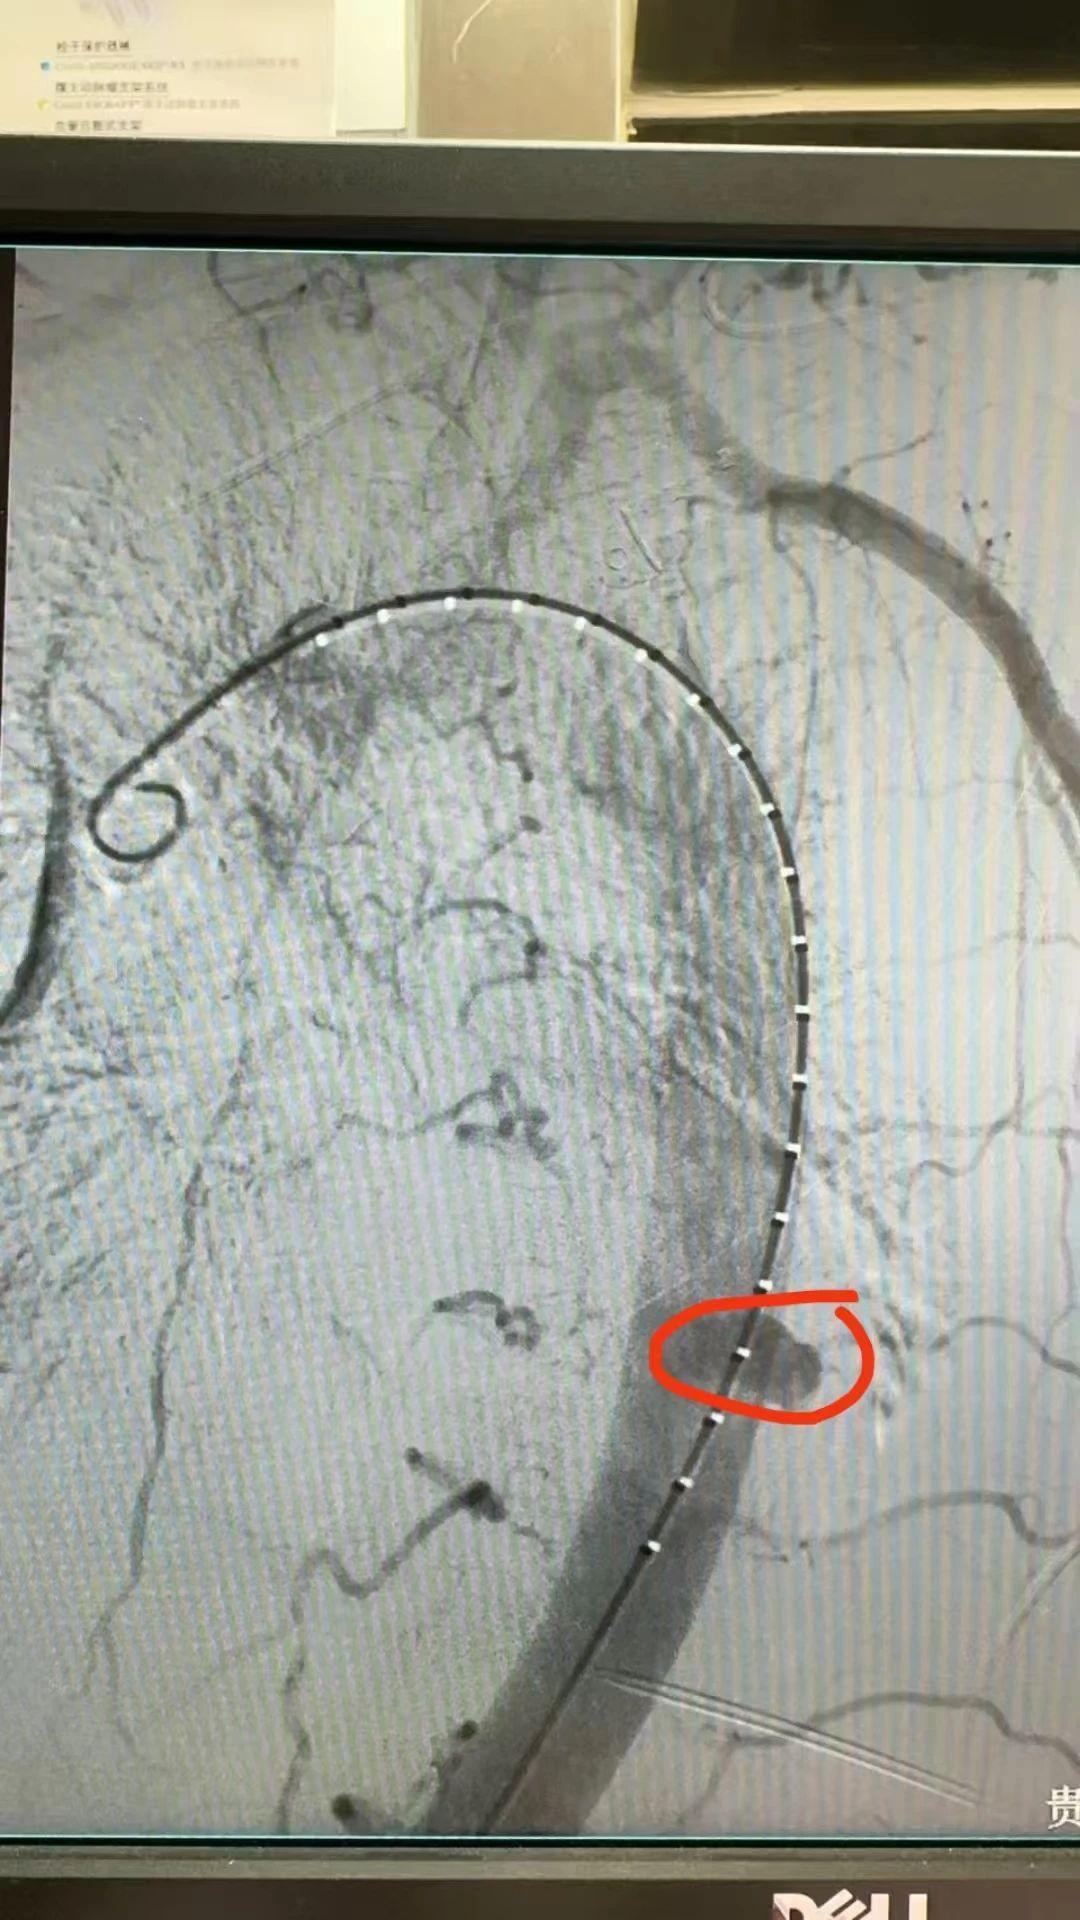

棘手的是,患者同时合并肾衰竭,且为乙肝患者,手术风险极高。心胸外科紧急联合肾内科、介入科、ICU、感染科等多学科开展大会诊,制定了周密的治疗方案:在透析与造影治疗间做好风险把控,既保证患者肾功能支持,又为手术争取到黄金时机。术后,患者被转入ICU,病情危重,医护团队全力救治。麻醉苏醒后,患者神志恢复清醒;术后第二天,胸痛症状显著缓解,无呼吸困难及大汗淋漓的现象,生命指标逐步向好。

术中造影发现破口